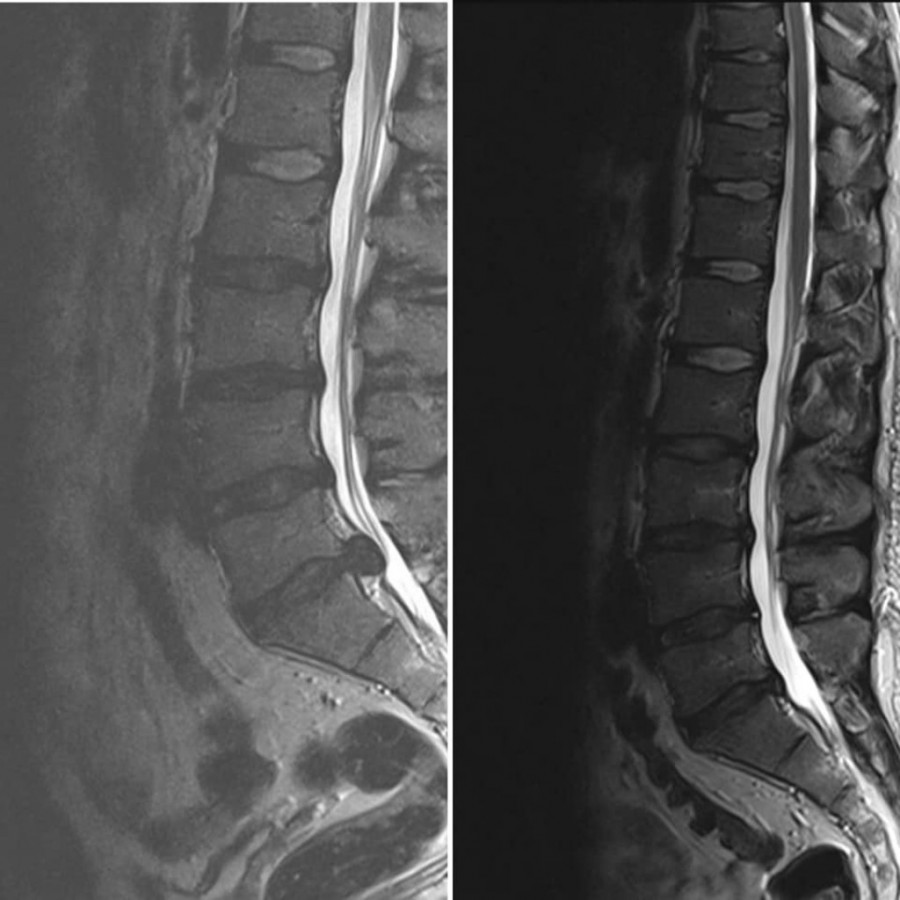

Dekompresijski tretman kičme ili DTK je jedini neoperativni tretman, kompjuterski kontrolisan i dijagnostički povezan, koji postiže odlične rezultate kod teških slučajeva diskus hernije, degenerativnih promena, artritisa, stenoze spinalnog kanala i pritiska na nervne korenove. Dekompresiona terapija kičme deluje tako da putem cikličnih faza distrakcije i relaksacije i pravilnom pozicioniranjem diska dovodi do povećanja međupršljenskog prostora za nekoliko milimetara (1-2), oslobađa živce - između njih, smanjuje bol, trnjenje, glavobolje, vrtoglavice, kao i slabosti u šakama i stopalima. Ovaj tretman stvara negativan pritisak i efekat vakuma u samom diskusu koji se nalazi između dva pršljena i na taj način povlači herniju unutar diska. Vakum povećava cirkulaciju oko diska i tako leči upalni proces. Dekompresijski tretman vrši istezanje receptora u mišićima i ligamentima oko kičmenog stuba, smanjuje pritisak na međupršljenske zglobove povećavajući pokretljivost kičme. Zatim odvaja, odnosno vrši separaciju pršljenova i povećava prostor između njih, proširenje intravertebralnog foramena i ispravljanje krivina kičmenog stuba. Klinički je dokazana efikasnost ove primene od 85 odsto.